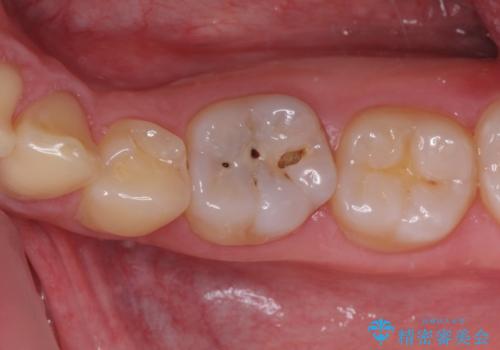

神経近くにまで及んだ大きなむし歯のセラミッククラウン

- 下顎左右奥歯に虫歯で痛みを感じるとのことで来院された患者様です。

むし歯が大きく、神経を取り除く可能性があることを理解いただいた上で虫歯を取り除き、その後はオールセラミッククラウンにて補綴することとしました。